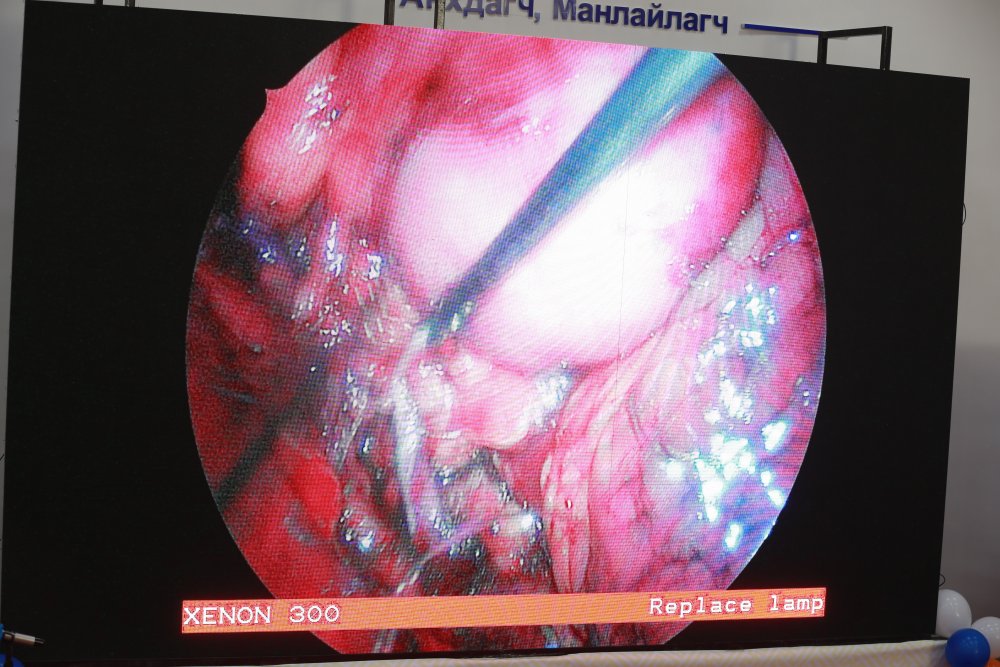

- Мэс заслын өрөө-1: Хэвлийн дурангаар бөөрийг бүхэлд нь авах мэс засал

- Мэс заслын өрөө-2: Хэвлийн дурангаар бөөрийг нөхөн сэргээх мэс заслыг БНСУ, БНХАУ-ын эмч, мэргэжилтнүүд хийж дуусгалаа.

- Мэс заслын өрөө-1: Хэвлийн арын зайгаар дурангаар бөөрийг нөхөн сэргээх мэс засал

- Мэс заслын өрөө-2: Бөөрний чулууг хатгалт-дурангаар авах мэс заслыг ГАДААД болон ДОТООДЫН эмч нар хамтран хийж байна.